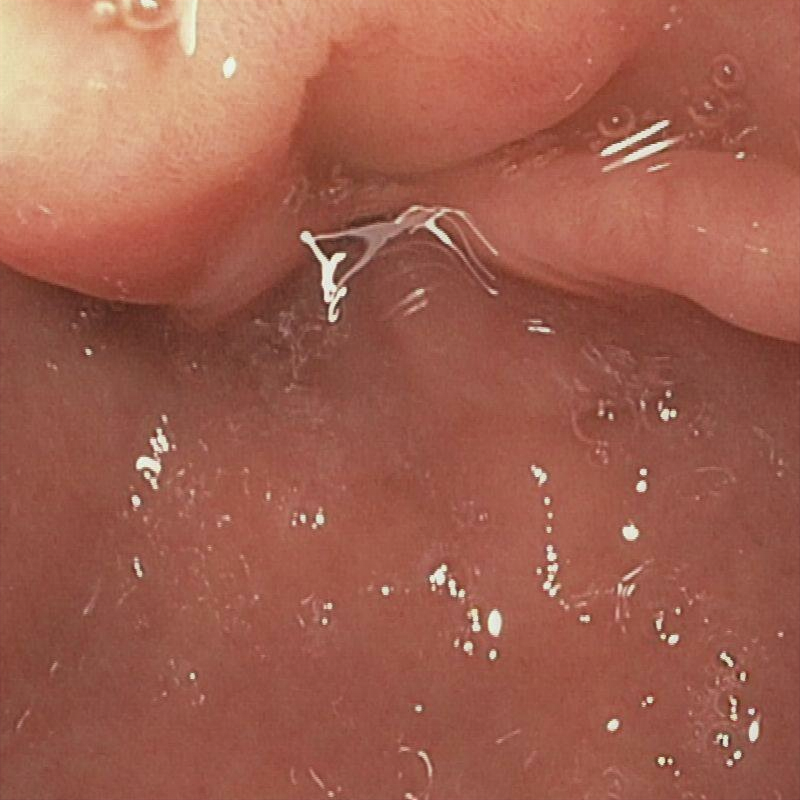

| (a) Input | (b) LIME | (c) HDRNet | (d) LECCM | (e) SwinIR | (f) NAFNet | (g) EndolMLE | (h) Ours | (i) GT |

The proposed method was evaluated on a synthetic dataset. All deep learning-based methods were fine-tuned based on E-kvasri. Figure 2 presents sample results of the proposed method and comparative methods on four endoscopic images from the E-kvasri.